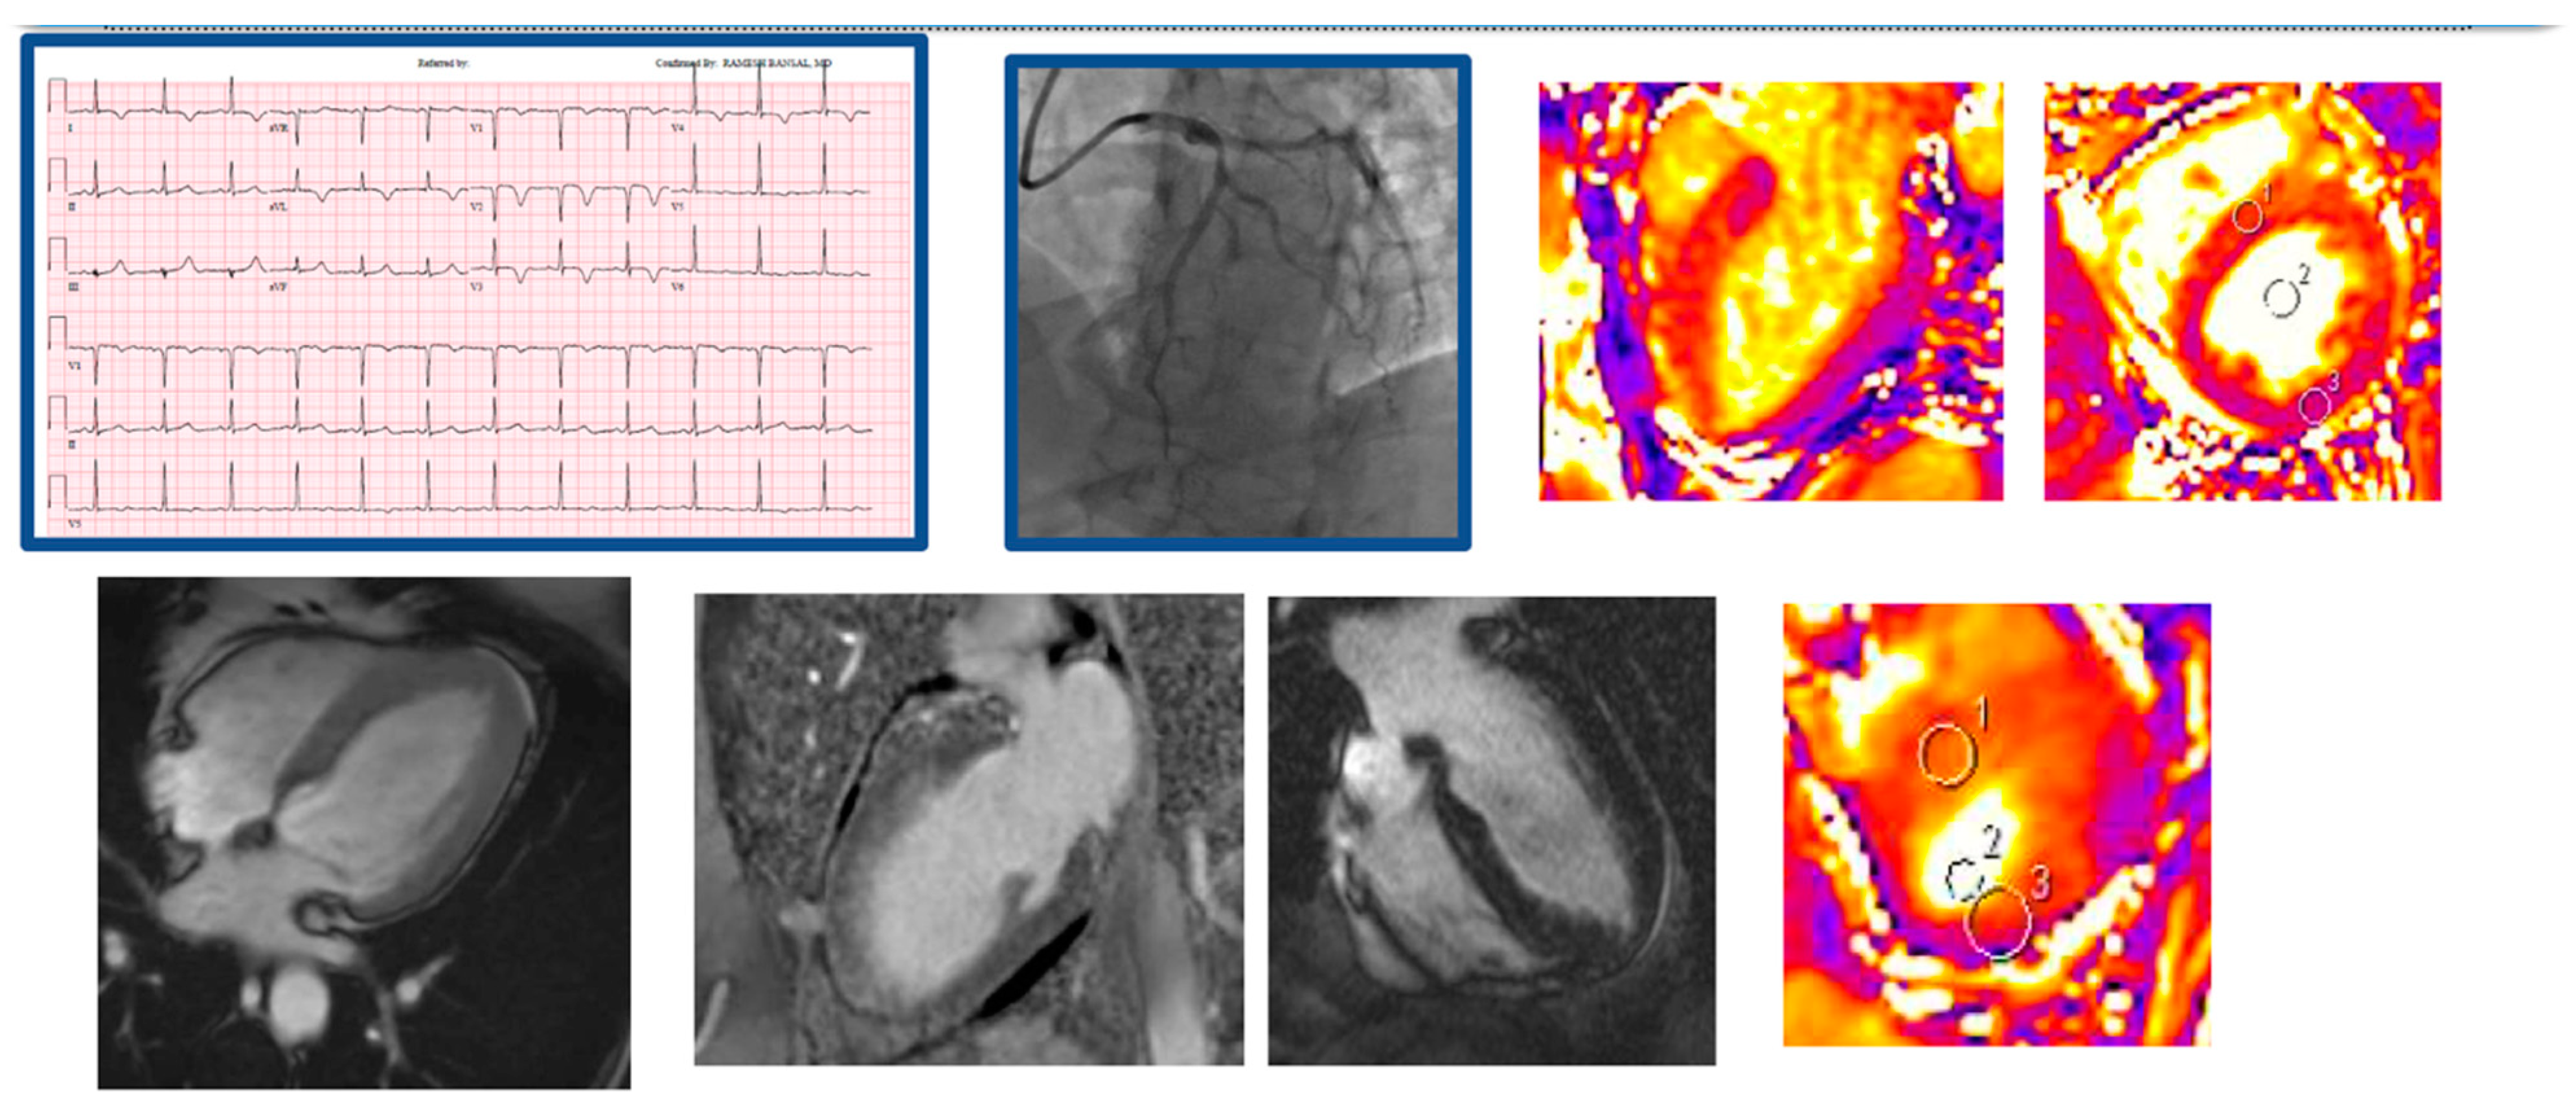

4. CMR in MINOCA: Timing, Protocol, and Diagnostic Possibilities

5. Myocarditis